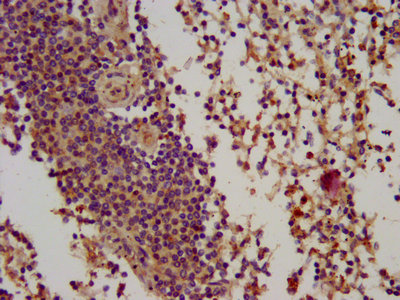

IHC image of CSB-PA002701LA01HU diluted at 1:100 and staining in paraffin-embedded human spleen tissue performed on a Leica BondTM system. After dewaxing and hydration, antigen retrieval was mediated by high pressure in a citrate buffer (pH 6.0). Section was blocked with 10% normal goat serum 30min at RT. Then primary antibody (1% BSA) was incubated at 4°C overnight. The primary is detected by a biotinylated secondary antibody and visualized using an HRP conjugated SP system.